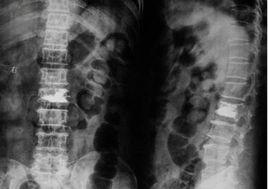

3.影像學改變 X線平片可清晰的顯示骨折線及其移位情況作為明確定位診斷,此外,尚應判定碎骨片(塊)侵入椎管的深度及範圍,對難以判定者,應常規行CT掃描或斷層攝影。

X線平片可清晰地顯示骨折線及其移位情況作為明確定位診斷,此外,尚應判定碎骨片(塊)侵入椎管的深度及範圍,對難以判定者,應常規行CT掃描或斷層攝影。